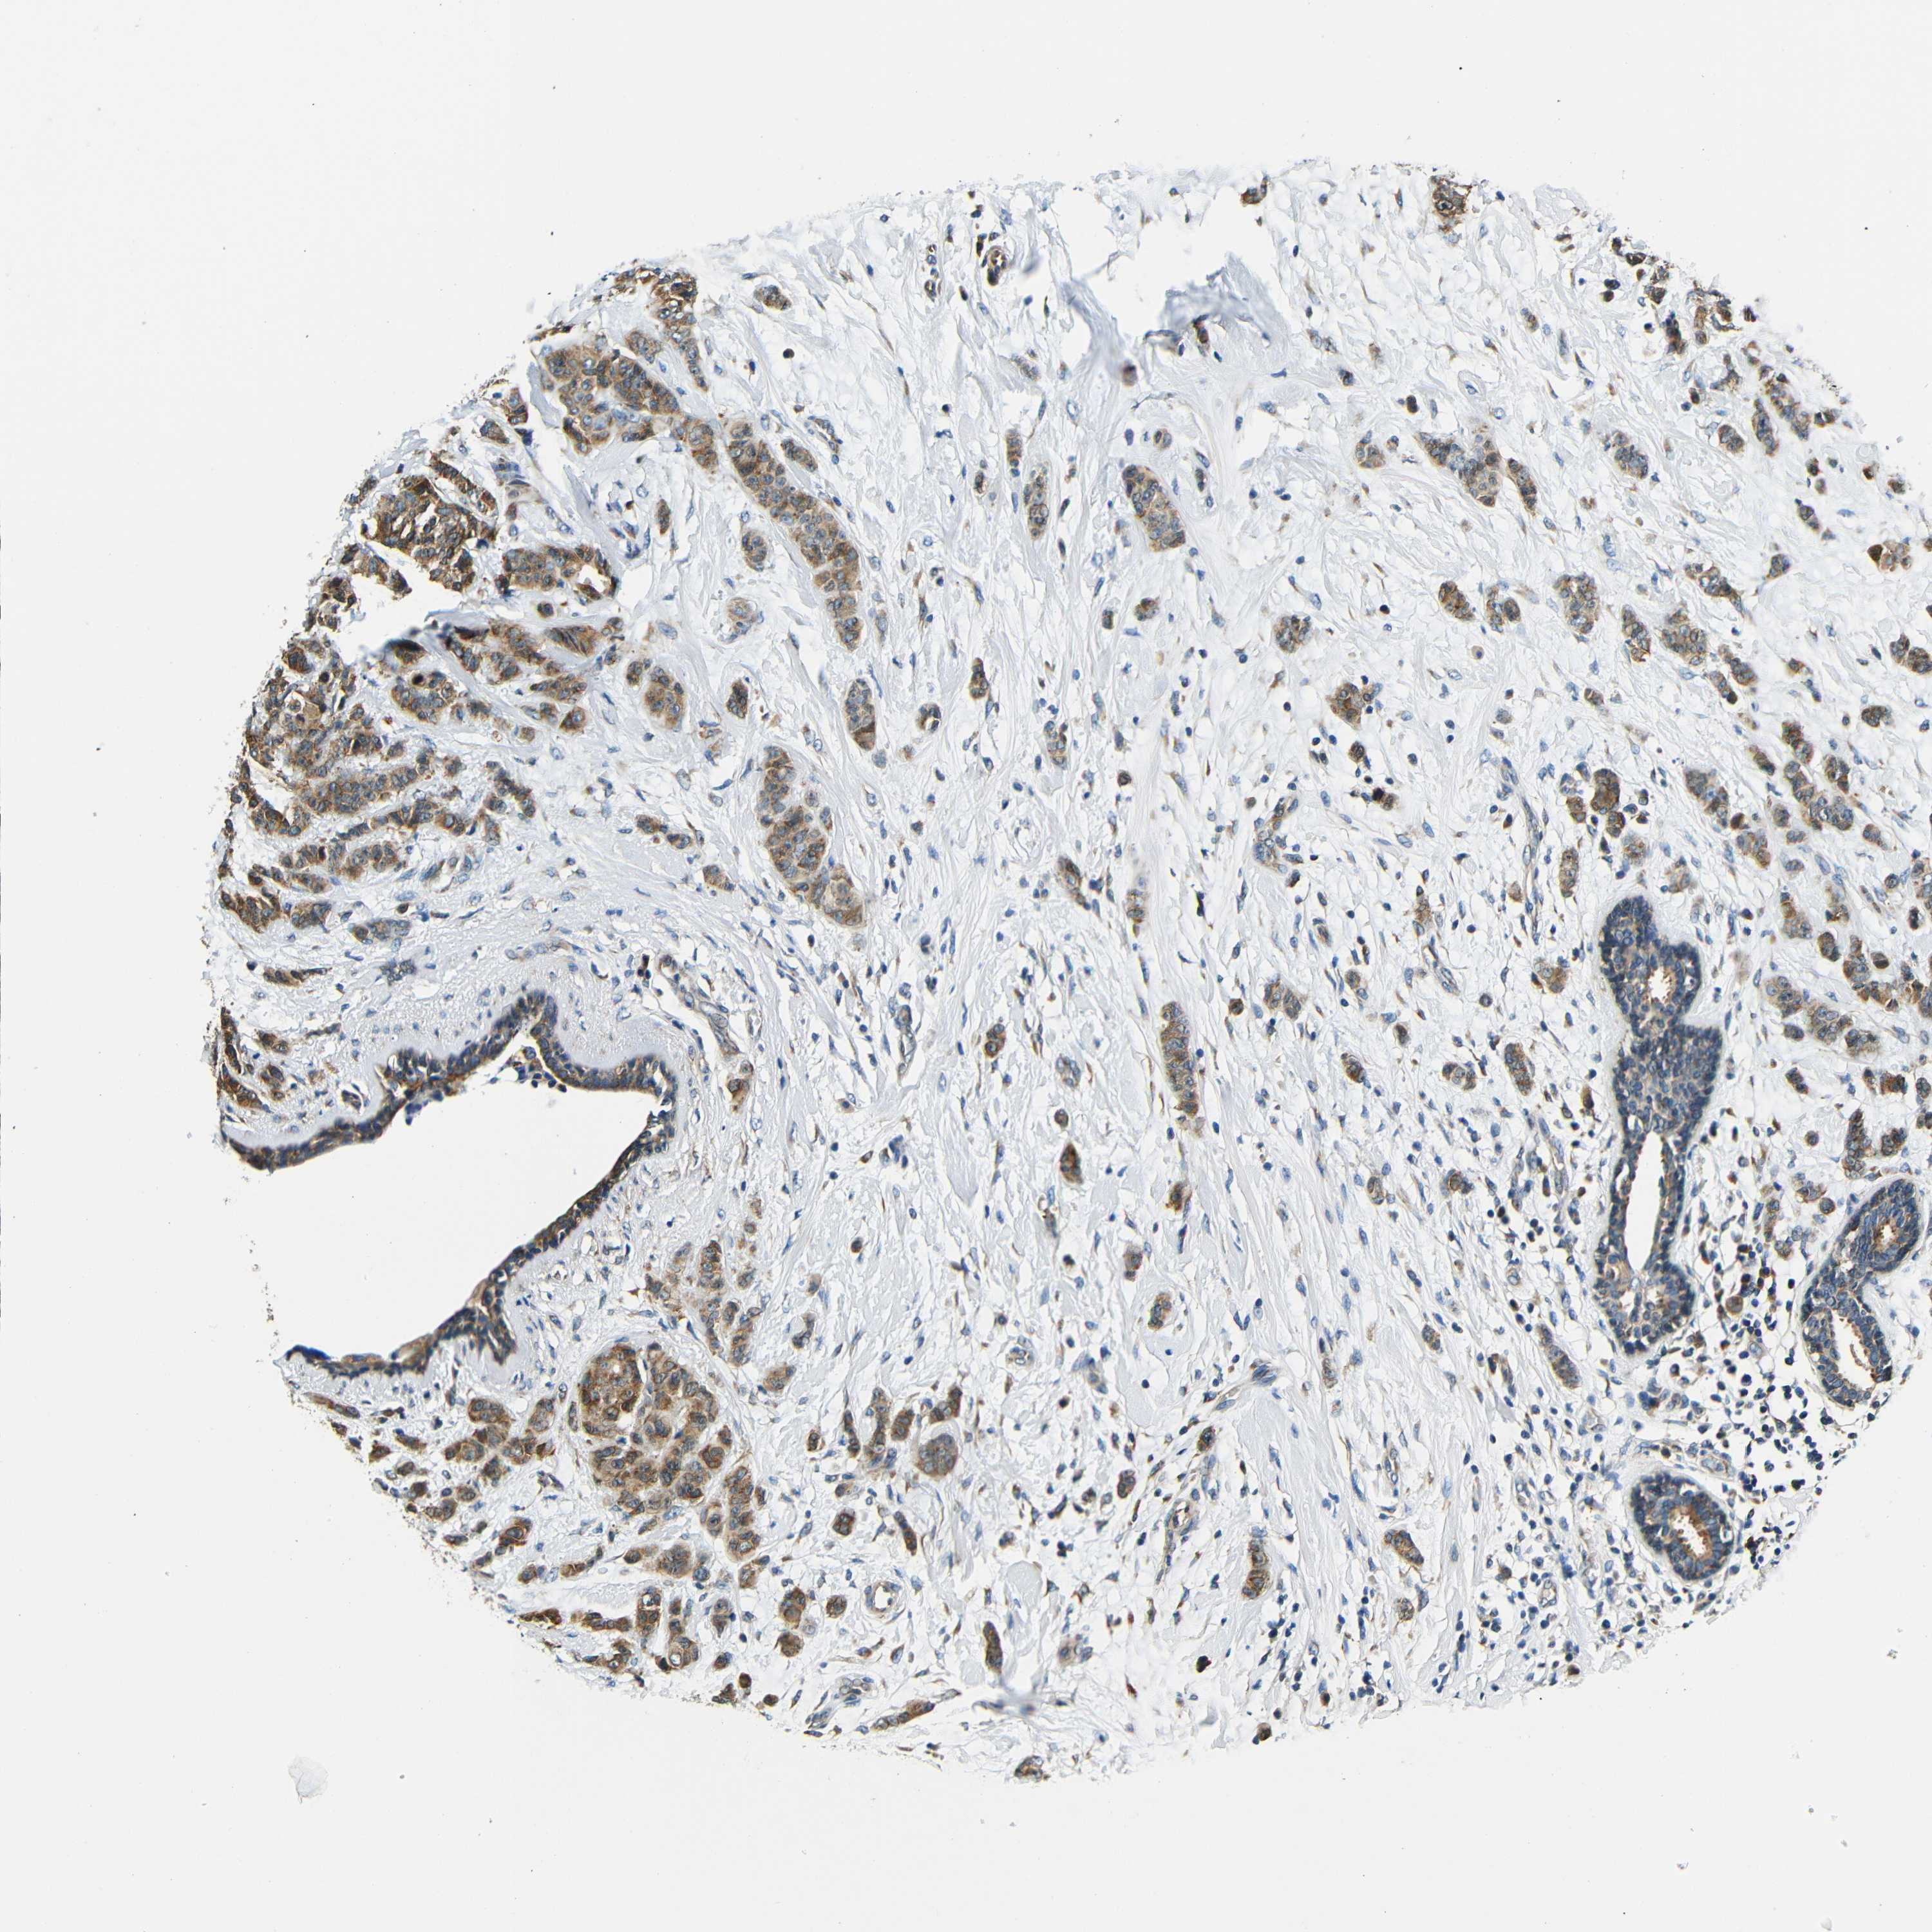

Breast cancer

Human cancer